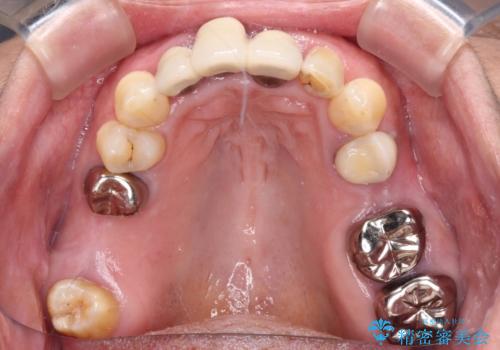

- 20年以上前に装着した前歯のメタルセラミックが不自然であることを気にして来院された患者様です。

歯肉の位置が変わり、変色した歯根が露出しているため、金属の土台をファイバーコアに交換した上で、オールセラミッククラウンにて補綴することとしました。

歯肉の位置は変更できないため、露出している歯根をクラウンで覆い隠すと歯が長く見えることを事前にお伝えしておりました。

真ん中2本は治療前よりも短めに仕上げることで、極端に長い印象を避けることができました。